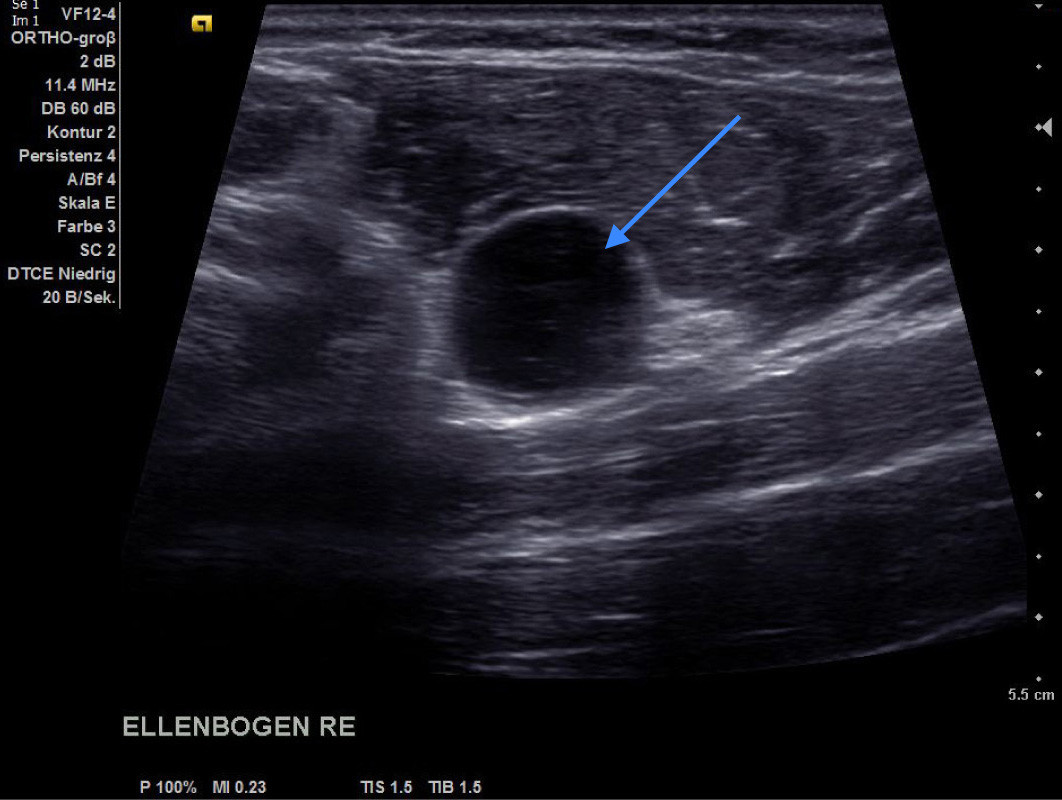

Diese Bild zeigt ein Gelenksganglion am Ellenbogen (Pfeil). Es sieht aus wie ein Ball und der Ultraschall geht komplett durch das Ganglion durch.